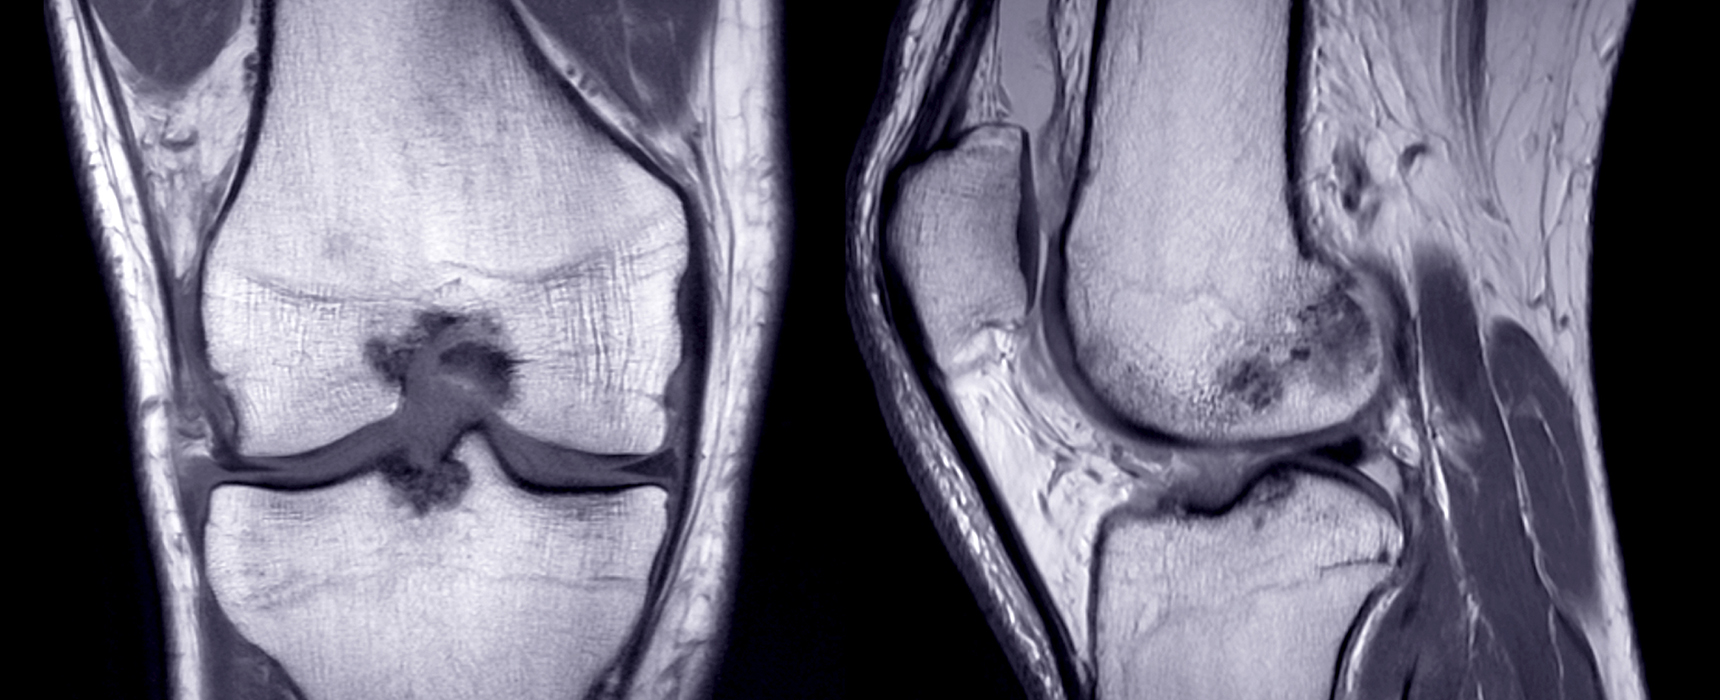

As the first disease-modifying therapies for osteoarthritis enter late-stage development, companies are testing new endpoints that can capture effects on joint structure instead of relying on traditional pain-related readouts. Most are converging on MRI imaging for its superior sensitivity to X-ray.